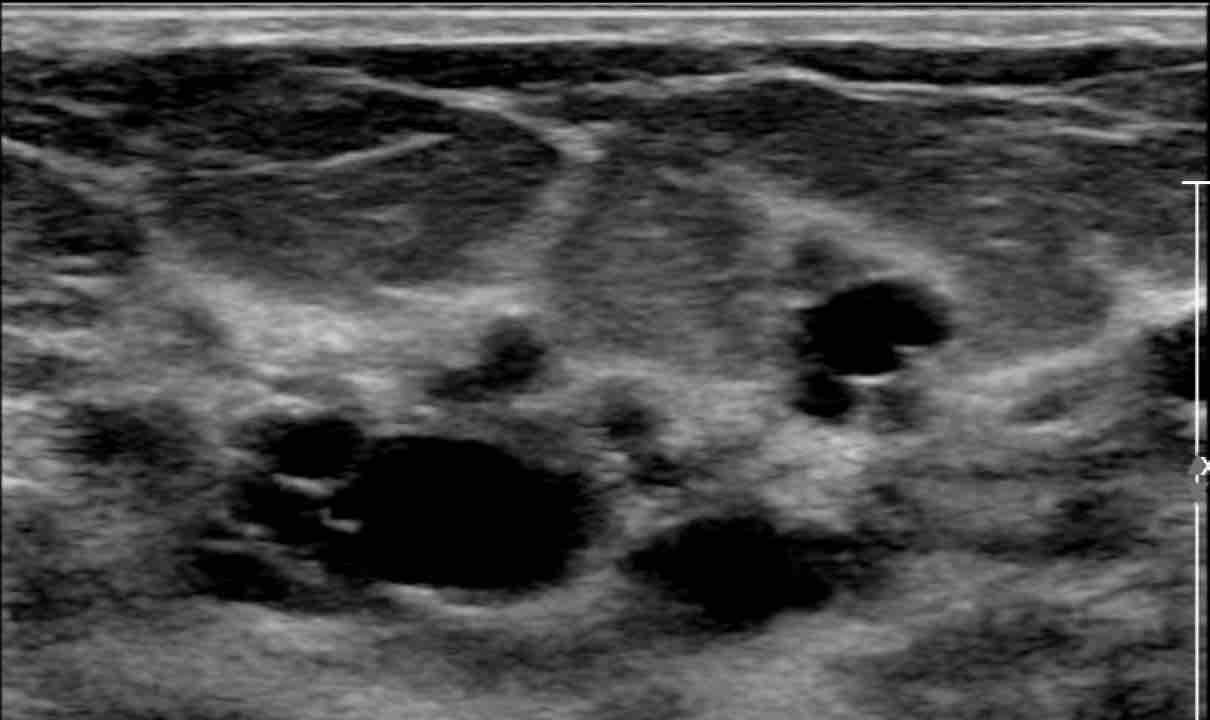

Người phụ nữ này có nhiều nang nhỏ ở cả hai vú.

Các nang này không sờ thấy được.